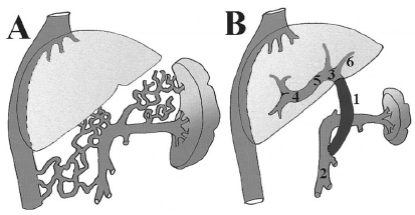

Наибольшей популярностью среди методов ПСР в настоящее время пользуется операция, предложенная в 1973 г М. Sugiura и S. Futagawa. В Японии она получила название "Метод Токийского университета", а в остальных странах известна как операция Sugiura

(рис. 5).

Рис. 5. Операция Sugiura.

Классическую операцию Sugiura выполняют в два этапа. На первом этапе производят торакотомию слева и перевязывают все коммуникантные ветви, идущие от расширенных венозных коллатералей, формирующих сплетение вокруг пищевода, сохраняя стволы блуждающего нерва и собственно параэзофагеальные коллатерали интактными. Затем пищевод пересекают выше или на уровне диафрагмы и накладывают анастомоз “конец-в-конец“. Второй этап выполняют из абдоминального доступа. Производят спленэктомию, полную деваскуляризацию абдоминальной части пищевода и кардиальной части желудка, селективную проксимальную ваготомию и пилоропластику. Операция Sugiura позволяет ликвидировать явления гиперспленизма; разобщить венозную систему пищевода и желудка с параэзофагеальными коллатералями; снизить объем интрамурального кровотока пищевода; сохранить параэзофагеальные коллатерали в качестве естественных шунтов.

В последующем, с целью упрощения операции, было предложено использовать механическое сшивающее устройство для наложения эзофагоанастомоза, накладывать циркулярный гемостатический шов через все слои стенки желудка, вместо пересечения пищевода, производить проксимальную селективную ваготомию, использовать фундопликацию по Toupet или Nissen для профилактики несостоятельности анастомоза и гастро-эзофагеального рефлюкса. Операцию в настоящее время проводят с использованием только абдоминального доступа.

Анализ результатов лечения более чем у 7000 больных, согласно данным Japanese Research Society for Portal Hypertension (JRSPH), показал, что вариант операции Sugiura, включающий трансабдоминальную деваскуляризацию пищевода на протяжении 8-10 см с использованием сшивающих аппаратов для наложения реанастамоза является в настоящее время наиболее популярным видом хирургического вмешательства при ВРВП в Японии. Проведенные в 1990 г. исследования JRSPH показали, что операции портосистемного разобщения эффективны и для профилактики первого кровотечения. В течение 5 лет наблюдения данное осложнение наблюдалось только у 7 % оперированных больных и в 46 % случаев у не оперированных.

Наиболее частыми осложнениями после операции Sugiura являются: транзиторная дисфагия, стеноз пищевода (2,5-4 %), несостоятельность анастомоза (6–7 %). Гастро-эзофагеальный рефлюкс у оперированных больных, при использовании одной из методик фундопликации, развивается редко (4 %). С другой стороны, у большинства больных через 6-7 лет после операций наблюдается рецидив ВРВП. Это объясняется образованием новых коллатеральных вен вокруг пищевода и верхней части желудка. Частота рецидивов кровотечений в отдаленном периоде после абдоминального этапа операции Sugiura, по данным разных авторов, составляет 25-35 %.

Исследования портального кровообращения в послеоперационном периоде показали, что операция Sugiura не ухудшает перфузию печени. В то же время отмечается снижение органного кровотока и тканевого насыщения кислородом в желудке, которые восстанавливаются к 7-му дню после операции. Эти данные говорят о том, что обширная деваскуляризация может привести к тканевой гипоксии желудка и вызвать геморрагический гастрит, который сам по себе может быть причиной послеоперационных кровотечений. Поэтому объем деваскуляризации должен быть выбран оптимально, чтобы стремление выполнить операцию радикально не привело к развитию геморрагического гастрита.

Операция Sugiura, вследствие своей травматичности не получила распространения в детской хирургии. В нашей клинике с этой целью используются операции лигирования на протезе, транссекции и реимплантации пищевода, обычно в сочетании с деваскуляризацией.